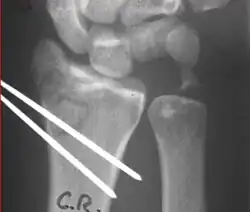

Surgery is generally indicated for displaced or unstable fractures.[18] The techniques of surgical management include open reduction internal fixation (ORIF), external fixation, percutaneous pinning, or some combination of the above. The choice of operative treatment is often determined by the type of fracture, which can be categorized broadly into three groups: partial articular fractures, displaced articular fractures, and metaphyseal unstable extra- or minimal articular fractures.[5]

Surgical options have been shown to be successful in patients with unstable extra-articular or minimal articular distal radius fractures. These options include percutaneous pinning, external fixation, and ORIF using plating. Patients with low functional demand of their wrists can be treated successfully with nonsurgical management; however, in more active and fit patients with fractures that are reducible by closed means, nonbridging external fixation is preferred, as it has less serious complications when compared to other surgical options.[5] The most common complication associated with nonbridging external fixation is pin tract infection, which can be managed with antibiotics and frequent dressing changes, and rarely results in reoperation.[5] The external fixator is placed for 5 to 6 weeks and can be removed in an outpatient setting.[5]

If the fractures are unlikely to be reduced by closed means, open reduction with internal plate fixation is preferred.[5] Although major complications (i.e. tendon injury, fracture collapse, or malunion) result in higher reoperation rates (36.5%) compared to external fixation (6%), ORIF is preferred, as this provides better stability and restoration of the volar tilt.[5][23] Following the operation, a removable splint is placed for 2 weeks, during which time patients should mobilize the wrist as tolerated.[5]